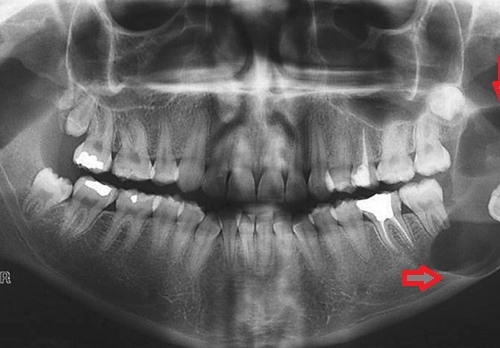

Normal halda insanın diş sırasında hər çənədə iki ədəd olmaqla, ümumilikdə dörd agıl dişi mövcuddur. Ağıl dişinin çıxması bəzi şəxslərdə heç bir kliniki əlamət və ya şikayətə səbəb olmasa da, bir çox hallarda müəyyən kliniki əlamətlərlə öyünü biruzə verir. Bu əlamətlər əsasən çənənin arxa tərəfində təzyiq, çənəni açıb baglama əsnasında agrı və məhdudlaşma kimi özünü göstərə bilir. Bu hallarda mütəxəssis konsultasiyasının önəmi olduqca böyükdür. Belə ki müayinə zamanı cərrah-stomatoloq kliniki və radioloji dəyərləndirmə apararaq dişin dogru pozisiyada yerləşib yerləşmədiyi, dişləmə çıxma ehtimalını, agıl dişinin çənəyə görə ölçüsü və çənə darlıgı kimi durumları dəyərləndirərək tətbiq edilməli olan müalicə taktikasını müəyyən edir.